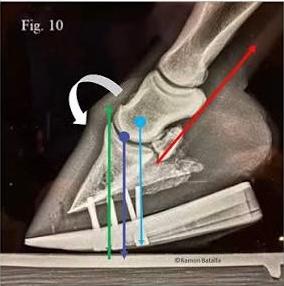

Biomechanical implications of full roller motion (self-adjusting palmar angle) shoes in equine palmar foot mechanics: theory, tendon and navicular orientation, and vectorial kinetics through stance phase. Author: Mark Caldwell PhD., FWCF., Niel Madden FWCF,. & Ronald Aalders * Scientific Horseshoein...

Biomechanical Rationale for Plantar Heel Extensions in the Management of Chronic Hindlimb Proximal Suspensory Desmopathy Caldwell M and Madden N. Scientific Horseshoeing Limited. 116, Newcastle Road, Talke, Staffordshire. ST71SA. Email info@hoofflix.com Introduction Chronic proximal suspensory ligam...

Chronic Proximal Suspensory Ligament Desmopathy in Horses: Biomechanics, Postural Adaptation, Hoof Capsule Morphology, and Treatment Strategies Caldwell M. N. Scientific Horseshoeing, 116, Newcastle Road, Talke, Staffordshire. ST7 1SA. Email info@hoofflix.com 1. Introduction Chronic desmopathy of th...